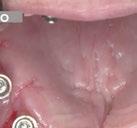

Acude a la consulta un paciente masculino de 35 años exigiendo cambios en la estética de sus dientes. El examen intraoral clínico y fotográfico reveló pérdida de estructura dentaria con facetas de desgaste en dientes anterosuperiores e inferiores, acentuándose hacia zonas oclusales de dientes posteriores.

El diagnóstico evidenció que el paciente presentaba alteración en la dinámica de la guía anterior por el desgaste de los bordes incisales, con pérdida de dimensión vertical oclusal (VDO), alteración del plano de oclusión y relaciones interoclusales inestables (Figuras 1 y 2)

Se obtuvieron modelos de estudio (Figuras 3-6) digitales mediante un escáner confocal de luz azul estructurada (PrimeScan, Dentsply Sirona) y se planificó un protocolo de desgaste mínimamente necesario y conservador de las estructuras

Figura 1. Caso inicial. Figura 2. Vista oclusal superior.